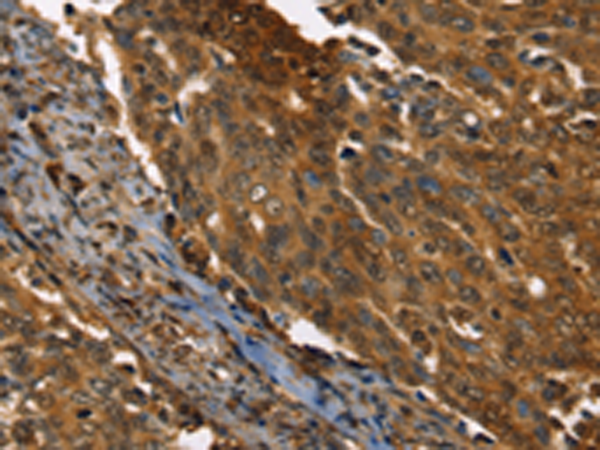

分类: 科研抗体货号: P08618别名: HPH2; PHD2; SM20; ECYT3; HALAH; HPH-2; HIFPH2; ZMYND6; C1orf12; HIF-PH2应用: IHC反应种属: Human, Mouse, Rat